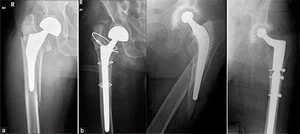

Нестабильность компонентов эндопротеза (асептическая нестабильность, расшатывание эндопротеза)

При стоянии или ходьбе на эндопротез ложится большая нагрузка, в соединении между костью и эндопротезом происходят микродвижения. Вследствие этого эндопротез расшатывается. Может расшататься как ножка (бедренный компонент), так и чашка (вертлужный компонент) протеза. Ножка эндопротеза может разрушить стенку кости, в которой расположена - возникает перипротезный (парапротезный) перелом.

При развившейся нестабильности эндопротеза требуется повторная операция - ревизионное эндопротезирование.

При перипротезном переломе потребуется операция остеосинтеза с последующим длительным ограничением физической активности.